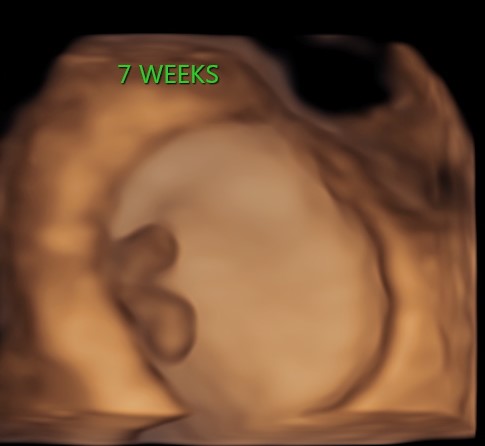

4D/5D/HD Ultrasound Gallery

Gallery